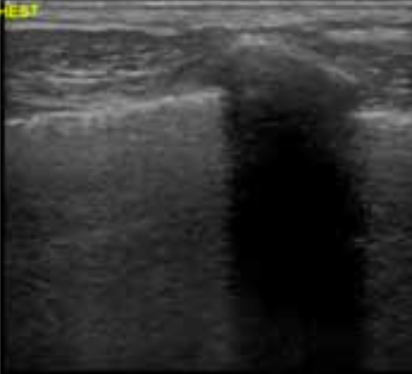

What would this look like if the patient had a pneumothorax?

Normally the visceral and parietal pleura slide against each other. If there is no sliding then you see no sliding and you look for the lead point. You can also use M-mode and look for sands on the seashore, if there are straight lines then you know there is no lung sliding and there is a pneumothorax.